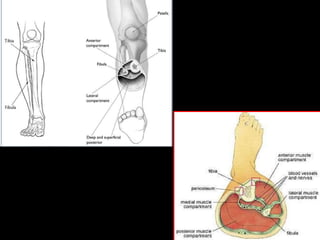

ACUTE COMPARTMENT SYNDROME

Increased pressure within a closed fascial spaces of the arm, leg

or other extremity, most often due to injury, exceeds the perfusion

Surgical treatment

• Vascular repair and fasciotomy

Fasciotomy of the Lower Leg